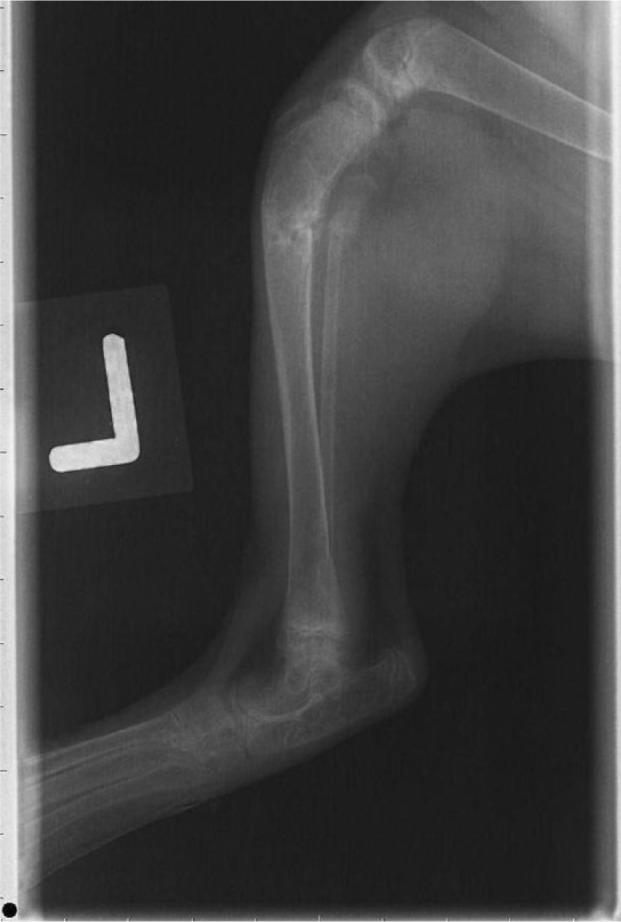

A 5-month-old castrated male Sphynx kitten presented with left hindlimb lameness shortly after adoption. Prior to adoption, the breeder had fed the kitten an exclusively raw chicken diet. Radiographs revealed generalized osteopenia and a left tibia-fibula fracture. Ophthalmic examination revealed corneal vascularization and opacity in the right eye, and lesions suggestive of feline central retinal degeneration in the left eye. The patient's diagnoses included metabolic bone disease and feline central retinal degeneration, which can result from taurine deficiency. The kitten's nutritional diseases were managed with a complete and balanced canned diet designed for kitten growth and with taurine supplementation.

一只5个月大的阉割雄性加拿大无毛猫幼猫在被领养后不久出现左后肢跛行。在被领养之前,繁育者一直只用生鸡肉喂养这只小猫。X光片显示全身性骨质减少以及左胫腓骨骨折。眼科检查发现右眼有角膜血管化和浑浊,左眼有提示猫中枢性视网膜变性的病变。该患者的诊断包括代谢性骨病和猫中枢性视网膜变性,这可能是由牛磺酸缺乏导致的。这只小猫的营养性疾病通过一种专为小猫生长设计的完全均衡的罐装食品以及补充牛磺酸来处理。